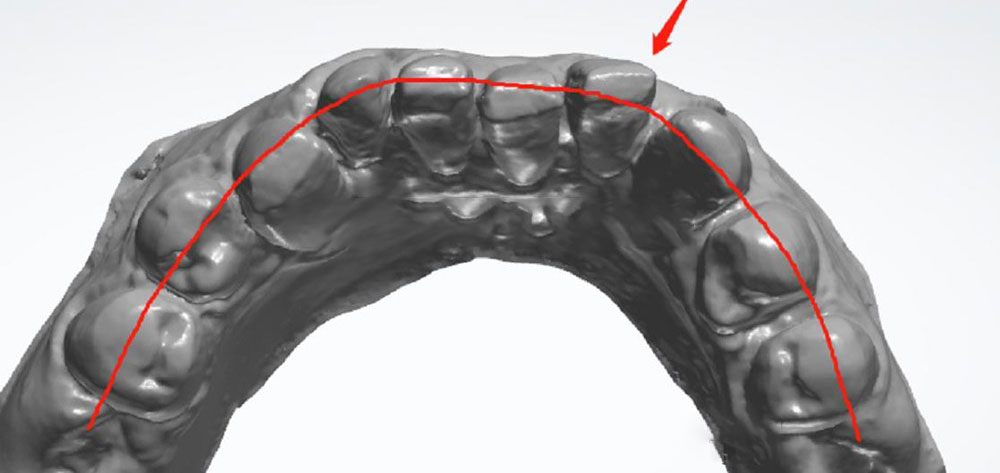

4. Try to create a nice arch

Please prepare teeth referring to the arch of jaw, so we can align teeth with crowns. Let’s take an example of the tooth in the picture above. The tooth (red arrow) is very bulky. The doctor could prepare more tooth towards the palatal, so we can try to make the tooth less bulky, and align other teeth.

A great tooth preparation should follow the alignment as much as possible